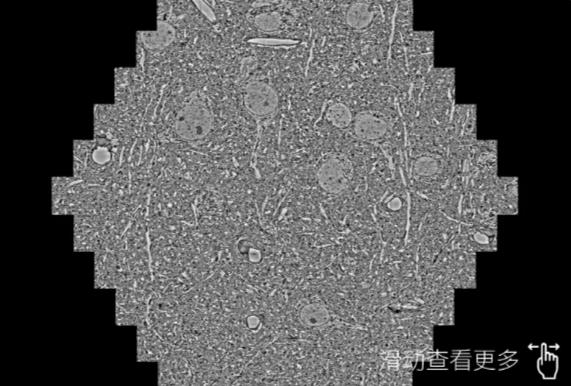

鼠脑切片。左图使用磐石蔡司磐石扫描电镜MultiSEM706对165μmx143pm面积区域成像,耗时仅需1.5秒。右图为鼠脑切片中30μm区域放大效果。样品由芝加哥大学B.Kasthuri提供。

使用蔡司高速磐石扫描电镜MultiSEM对1mm²人脑皮层组织进行高分辨成像,并对其中的各种细胞结构进行三维重构分析。左图展示了2x3mm²组织平面中锥体神经元的三维重构效果。右图显示了局部体积神经元三维重构。图像由哈佛大学chtman实验室提供,渲染图由D. Berger 制作。